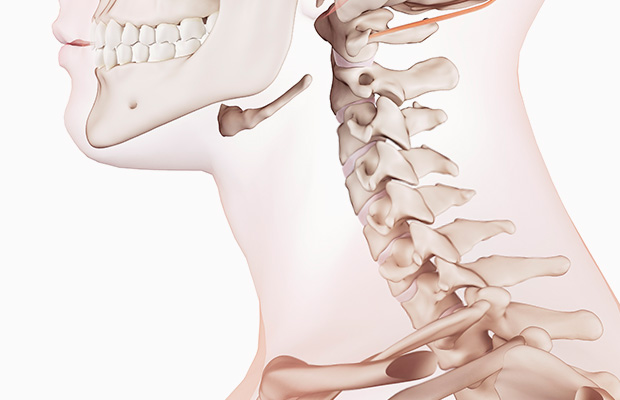

목디스크란 목뼈 사이에 있는 디스크가 손상되어 신경을 압박하는 질환을 의미합니다. 디스크는 젤리와 같은 수핵과 섬유륜으로 구성되어 있습니다. 섬유륜이 손상되면 수핵이 밖으로 밀려나와 신경을 압박하게 됩니다.

목 디스크에 가해지는 부담을 줄이기 위해서는 바른 자세를 취하고 유지하는 것이 가장 중요합니다. 앉거나 서 있을 때는 척추를 곧게 펴고 어깨에 힘을 빼고 머리가 목 위에서 균형을 이루도록 합니다.

구부정하거나 앞으로 구부정한 자세는 경추 디스크에 과도한 스트레스를 줄 수 있으므로 피해야합니다.